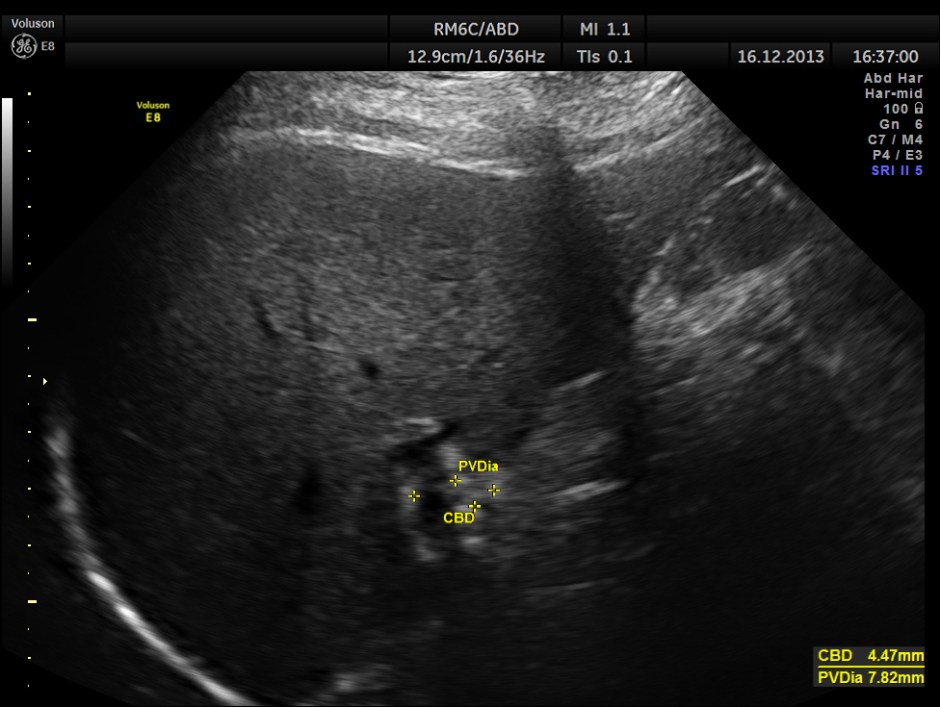

This was a 63-year-old gentleman who came for recurrent episodic right upper quadrant pain of 2 to 3 weeks duration.On examination Murphy’s sign was positive. The pictures follow.

The Common Bile Duct is 5.07 mms.

Now a quick question . What is the normal range of measurement of the C.B.D. ?

a small although statistically significant increase in the caliber of the common bile duct with increasing

age (60 years old or less, mean diameter 3.6 mm ± 0.2mm, versus over 85 years old, mean diameter 4

mm ± 0.2 mm, P = 0.009). Although the common bile duct did increase in size with aging, 98% of all

ducts remained below 6 to 7 mm, the commonly accepted upper range of normal.

The C.B.D. measured 5.70 mms ( still within the normal range ).There was no evidence of any obstruction .